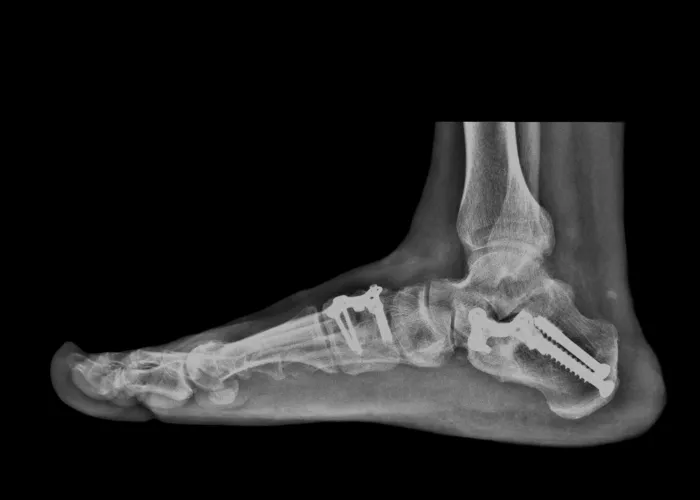

There are variety of things that can happen that cause those ligaments to stretch, causing them to lose their ability to support the foot as they should. This can lead to pes planus (flatfeet), also known as fallen arches. Most people don’t realize that there are actually three arches in the foot, not just one: lateral, medial, and anterior.

Bones that are dislocated or broken